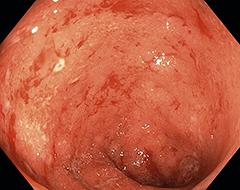

Colitis ulcerosa is een chronische darmziekte, die samen met de ziekte van Crohn valt onder de noemer IBD (irritable bowel diseases). Colitis ulcerosa kenmerkt zich door buikpijn, diarree, toegenomen ontlastingsfrequentie, bloed en slijm bij de ontlasting, verminderde eetlust en afvallen. Deze klachten hoeven echter niet allemaal aanwezig te zijn. In dit artikel wordt de casus van Anne, een vrouw van 27 jaar met colitis ulcerosa, volgens een aantal diagnostische stappen besproken. Er wordt onder andere ingegaan op de classificatie van colitis ulcerosa en de daarop gebaseerde behandeling.